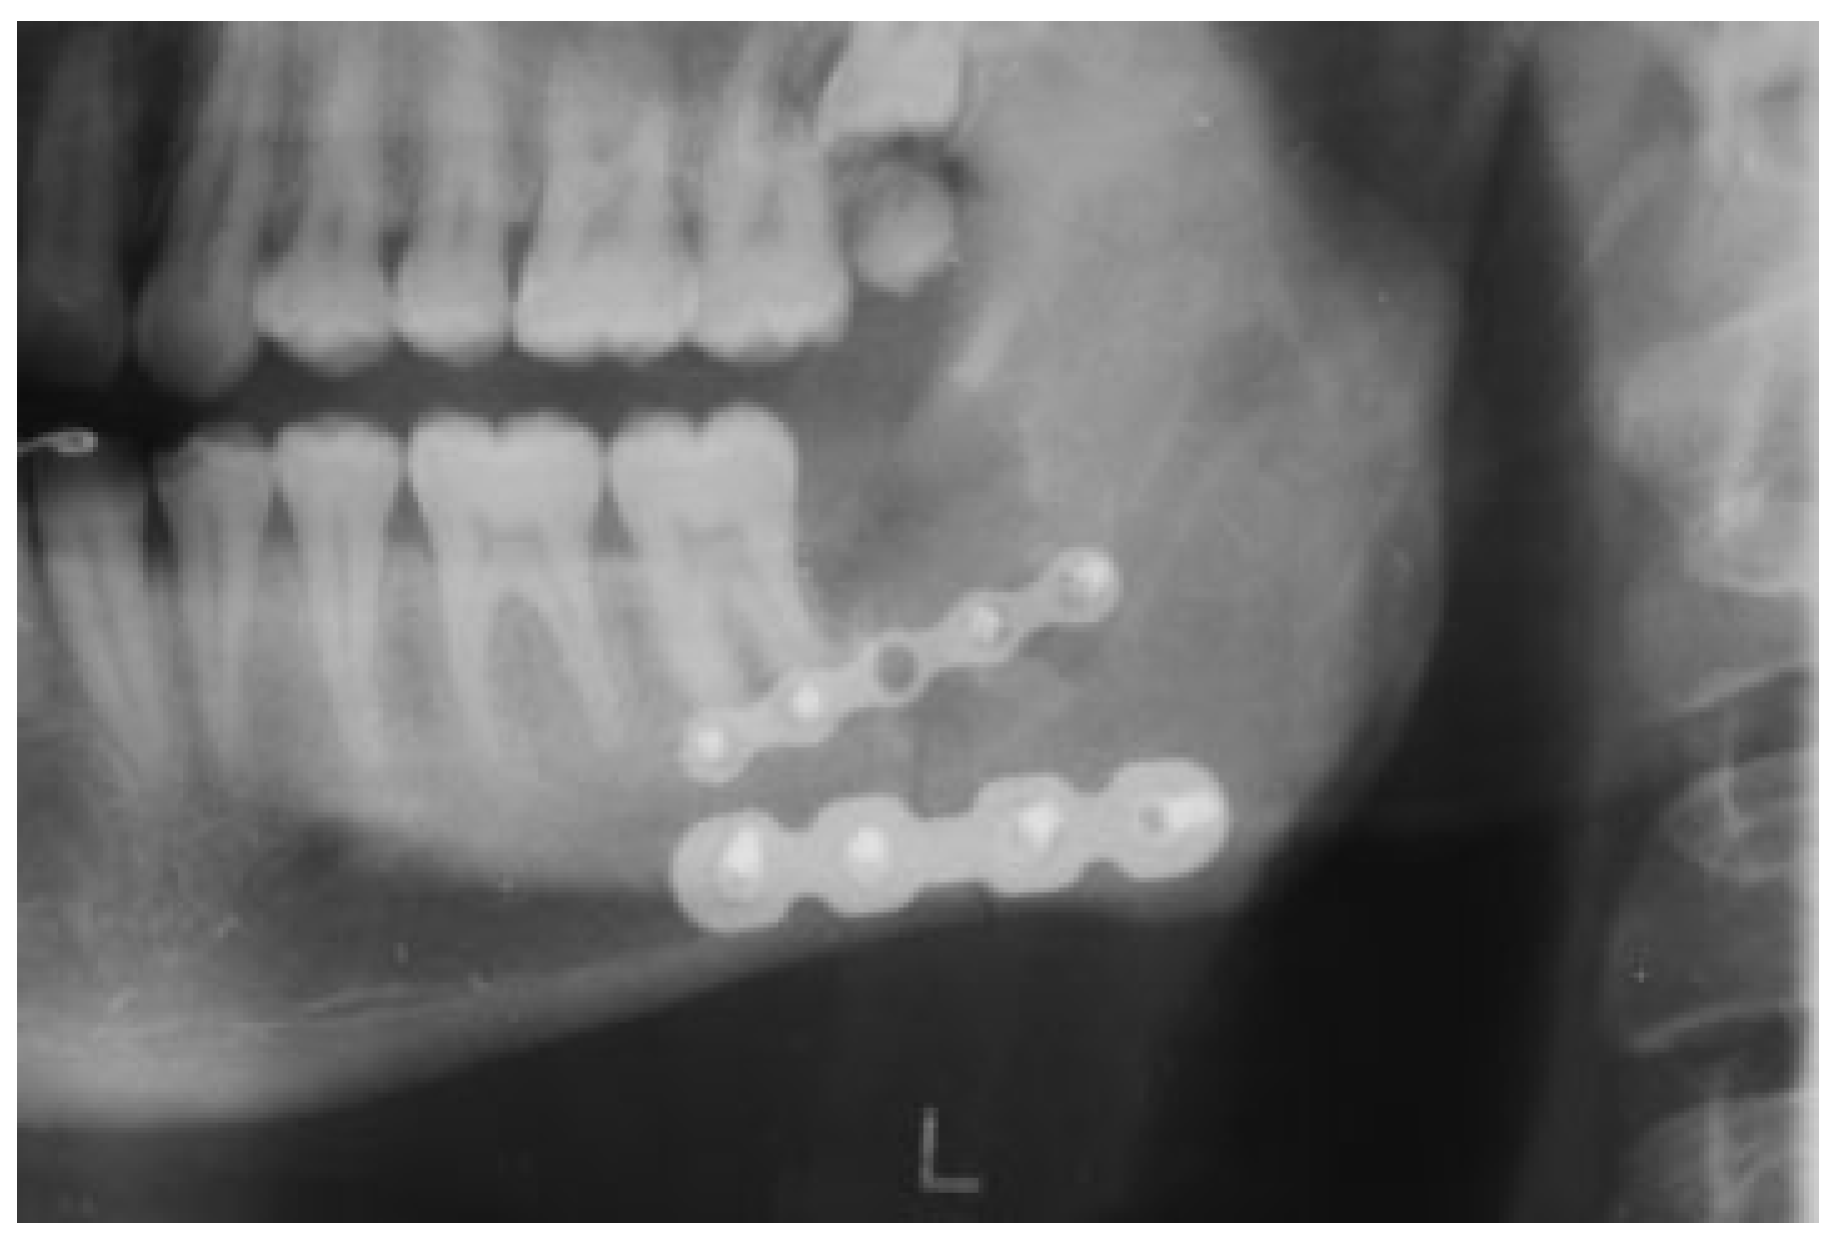

1.3. Case 3